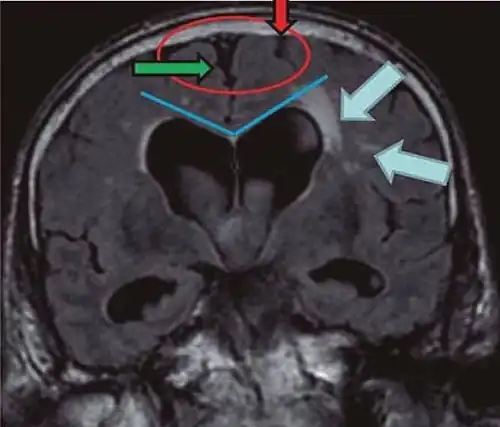

- Imaging from magnetic resonance imaging (MRI) or computed tomography (CT) is needed to demonstrate enlarged ventricles and no macroscopic obstruction to cerebrospinal fluid flow. Imaging should show an enlargement to at least one of the temporal horns of lateral ventricles, and impingement against the falx cerebri resulting in a callosal angle ≤ 90° on the coronal view, showing evidence of altered brain water content, or normal active flow (which is referred to as "flow void") at the cerebral aqueduct and fourth ventricle.

| Normal pressure hydrocephalus | Brain atrophy | |

| Preferable projection | Coronal plane at the level of the posterior commissure of the brain. | |

| Modality in this example | CT | MRI |

| CSF spaces over the convexity near the vertex (red ellipse |

Narrowed convexity ("tight convexity") as well as medial cisterns | Widened vertex (red arrow) and medial cisterns (green arrow) |

| Callosal angle (blue V) | Acute angle | Obtuse angle |

| Most likely cause of leucoaraiosis (periventricular signal alterations, blue arrows |

Transependymal cerebrospinal fluid diapedesis | Vascular encephalopathy, in this case suggested by unilateral occurrence |

MRI scans are the preferred imaging. The distinction between normal and enlarged ventricular size by cerebral atrophy is difficult to ascertain. Up to 80% of cases are unrecognized and untreated due to difficulty of diagnosis.[22] Imaging should also reveal the absence of any cerebral mass lesions or any signs of obstructions. Although all patients with NPH have enlarged ventricles, not all elderly patients with enlarged ventricles have primary NPH. Cerebral atrophy can cause enlarged ventricles, as well, and is referred to as hydrocephalus ex vacuo. For these reasons it's utmost important to note that Evan's index although commonly used in imaging is not very specific for NPH. One recent systematic review and meta-analysis suggests that callosal angle has high diagnostic performance and is commonly used together with Evan's index.[23]